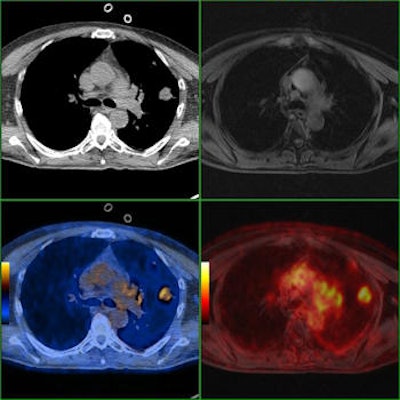

Comparison of PET/CT and PET/MRI of a patient with a solitary lung metastasis showing superiority of CT versus MRI. Axial CT and axial PET/CT images show the large metastasis in the left lung. The lesion is only detectable in co-registered PET/MRI images but undetectable on the MRI.